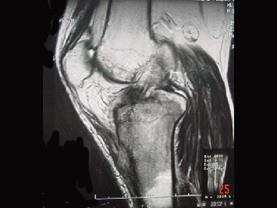

问题 患者女,28岁,右膝跌伤伴疼痛9年,加重及活动障碍1年半,经药物治疗及理疗后病情无好转,既往无特殊病史,查体跛行步态,触痛,请结合所提供的图像,选择最佳选项 ( )

选项 A、软骨肉瘤 B、骨巨细胞瘤 C、滑膜肉瘤 D、骨肉瘤 E、结核

答案 C